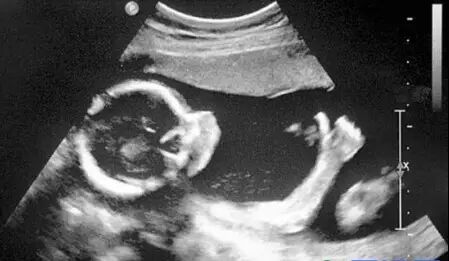

B超:像挑西瓜前敲一敲

B超的原理是用超声波穿透人体,当声波遇到人体组织时会产生反射波,通过计算反射波成像。就像挑西瓜一样,边敲边看显示病灶情况。